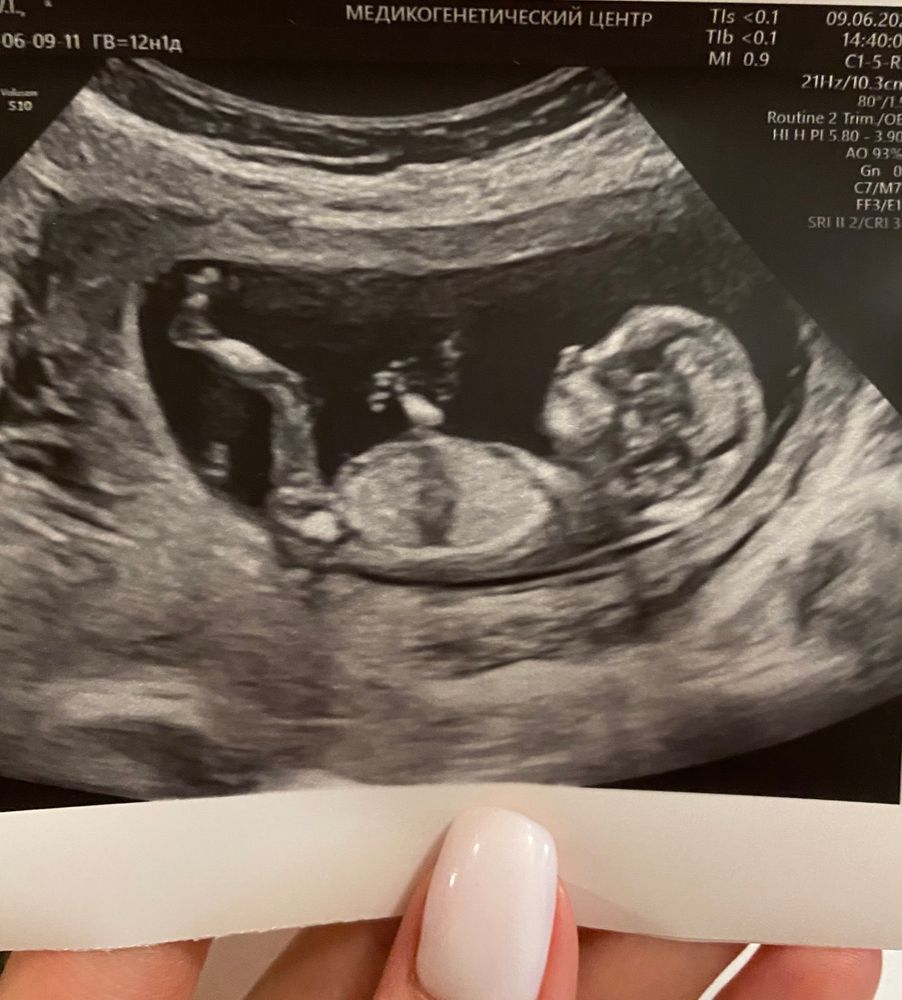

Первый скрининг пройден🌸🎀

Ох как же прекрасно все это ощутить еще раз.Все по узи прекрасно.Опережает лялечка на неделю.Наверное овуляция была очень ранней.По М 12 недель,по ктр 13 ровно.Иии,будет ДЕВОЧКА))))Господи,как я счастлива🌸😊.Конечно,был бы второй мальчишка,тоже прикольно и я была бы рада,но когда разнополые детки-это здорово наверное))Теперь жду кровь,но думаю там все будет хорошо)

Ну а шейка как всегда короткая.27.пришли мы к выводу,что это моя особенность.Будем перемерять в 16 недель